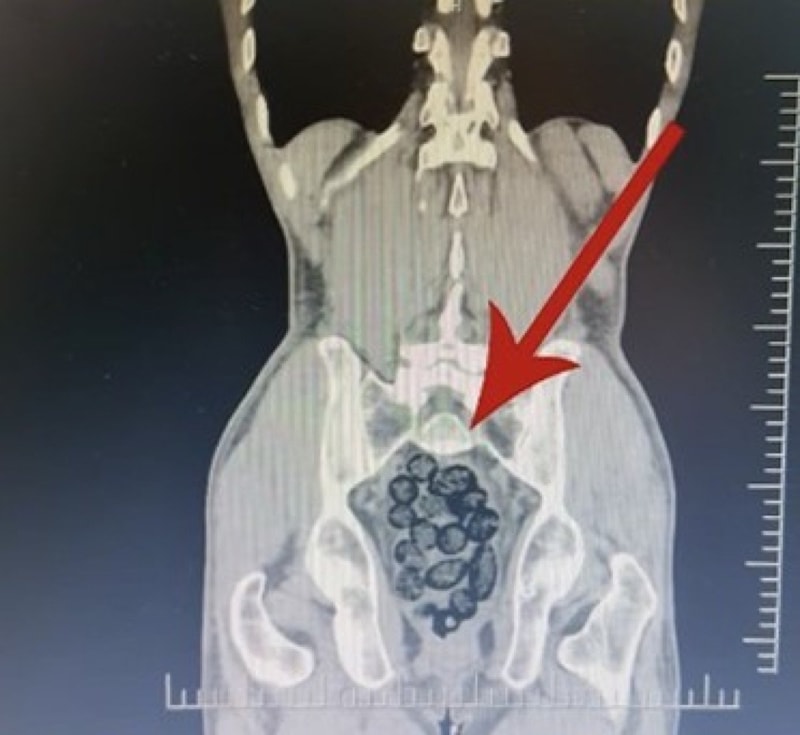

Yapılan incelemeler sonucunda yabancı uyruklu şahsın midesinde, 64 parça halinde toplam 472 gram uyuşturucu maddesi metamfetamin olduğu belirlendi.

Gözaltına alınan şahsın midesindeki uyuşturucu madde çıkartıldı.